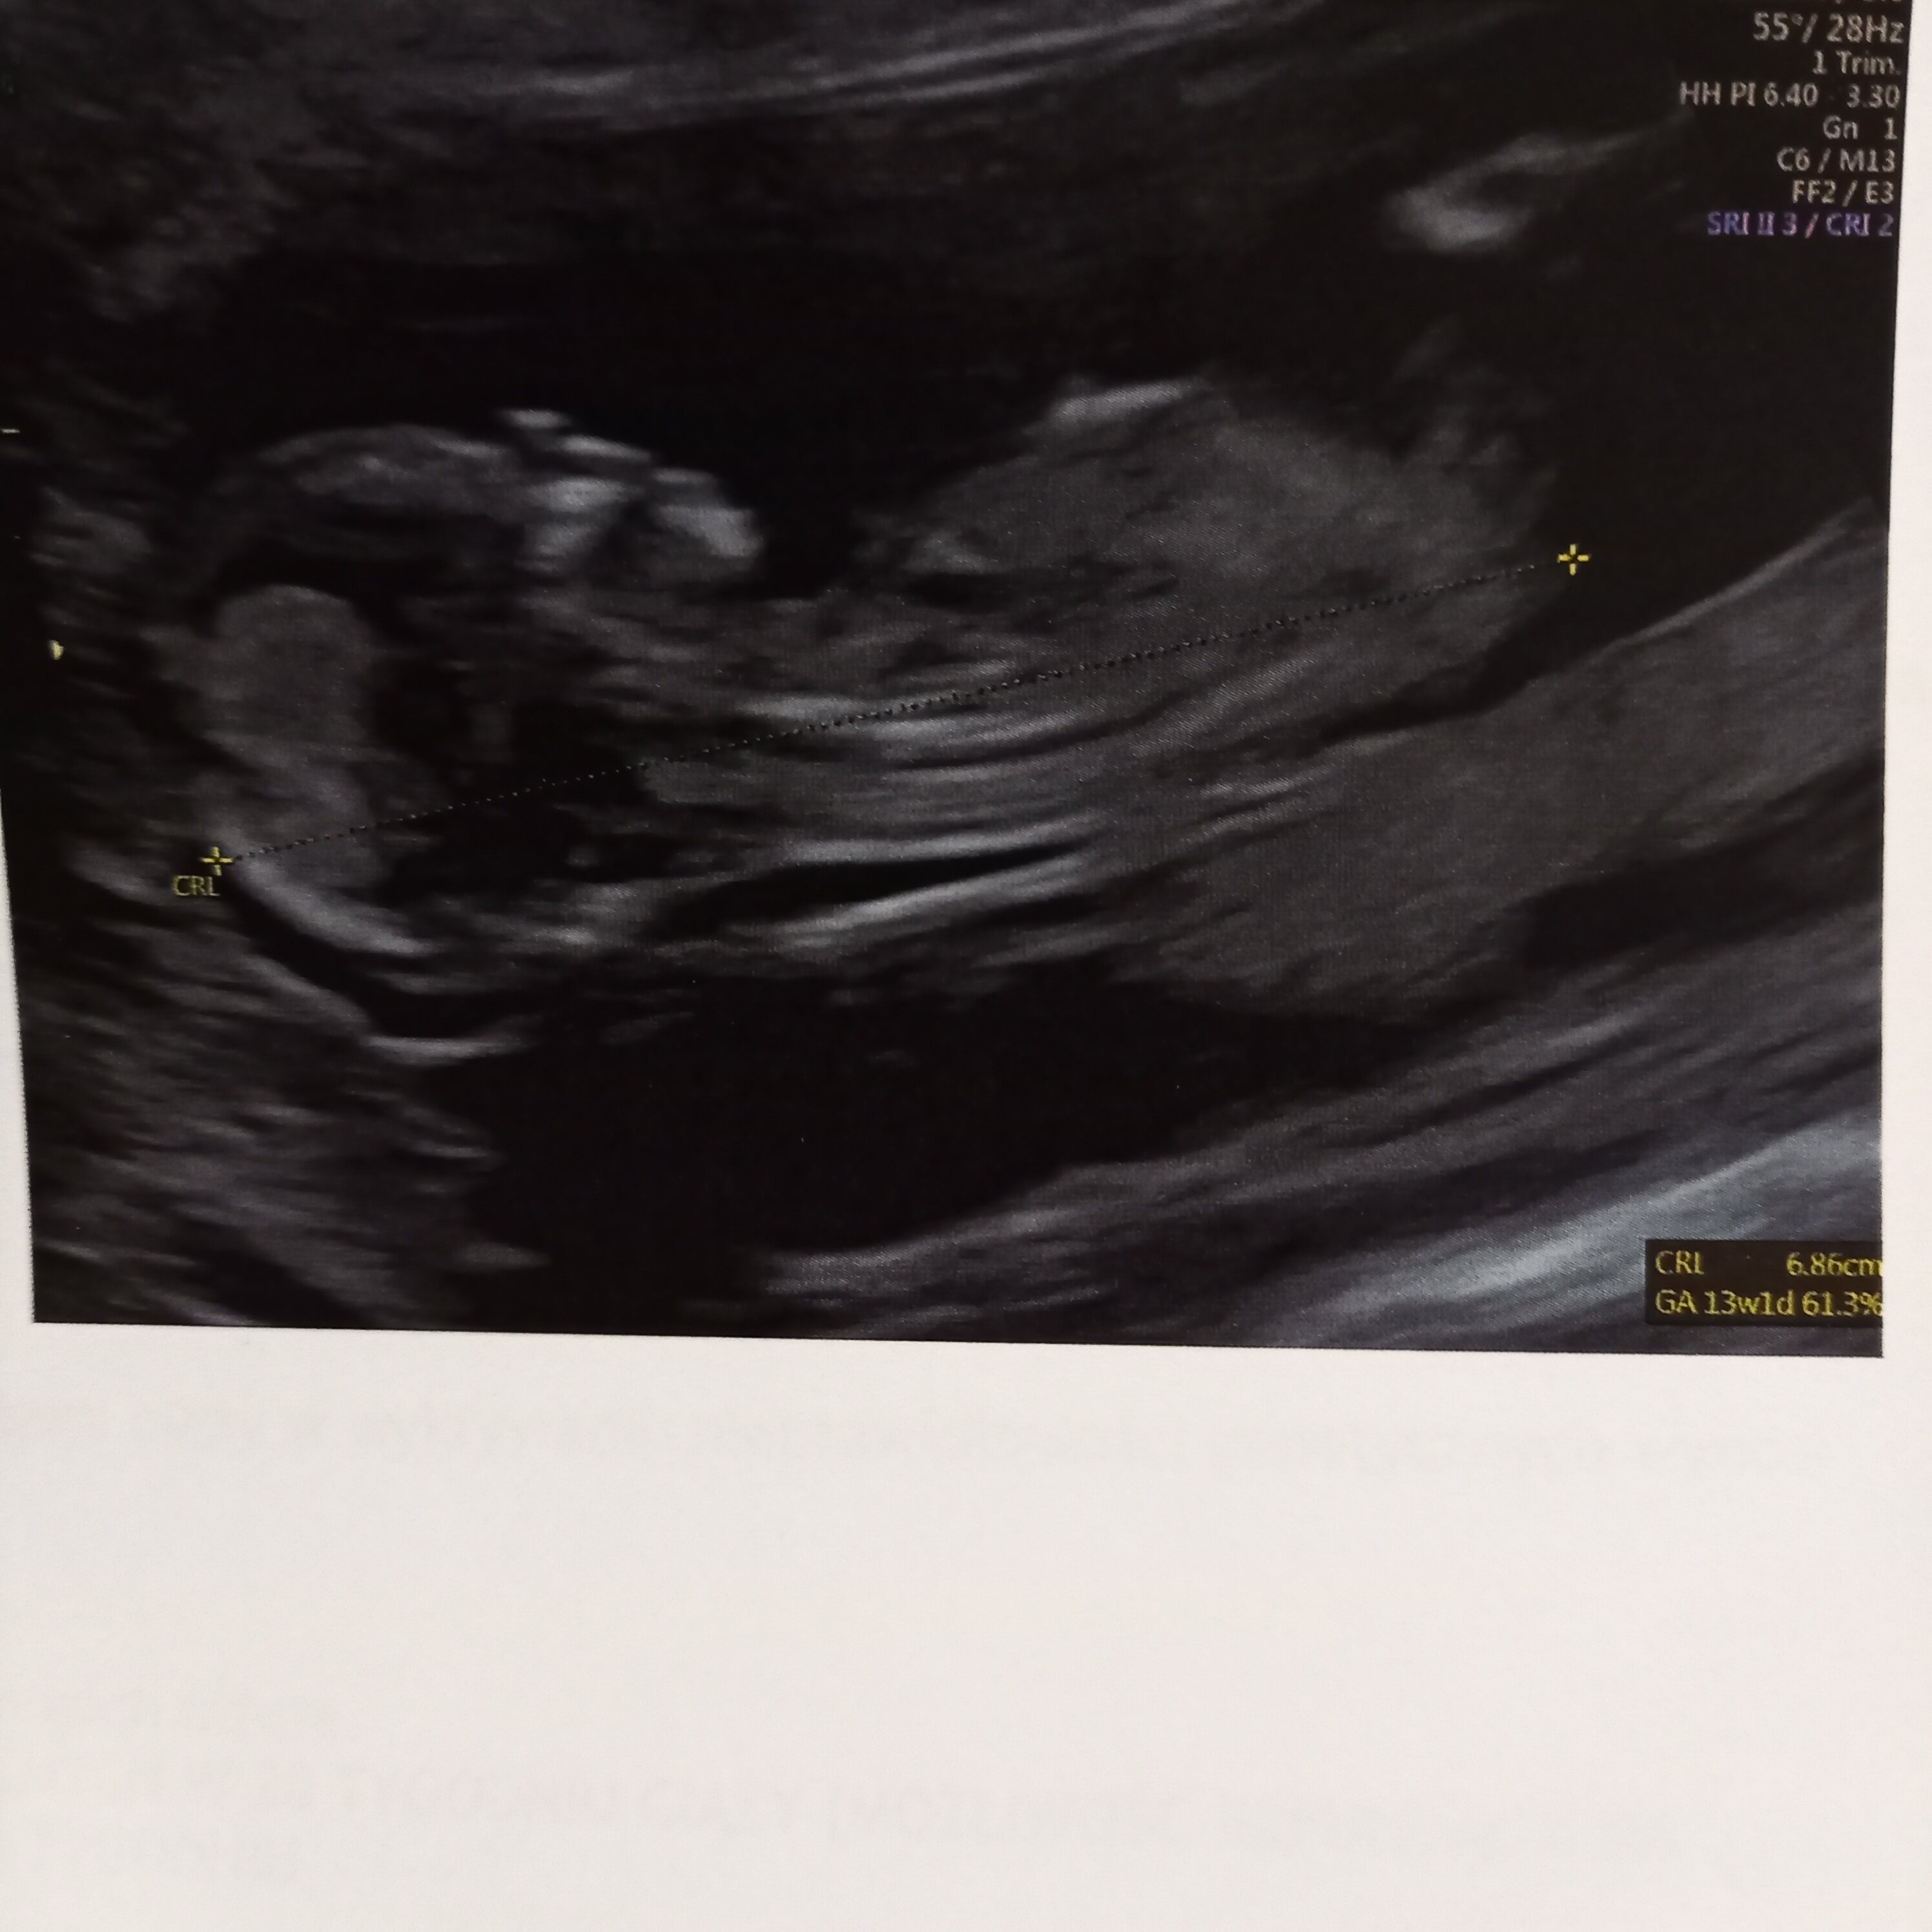

No i po badaniu... szczerze mówiąc to lekarz nic mi nie powiedział czy jest dobrze czy nie bo mam czekać na wyniki pappa i wtedy dostanę konkretne informacje... Z ciekawostek to z nifty dziewczynka a on mi mowi że 90% chłopiec... także hmmm komu bardziej ufać? Idę do swojego lekarza we wtorek to podpytam... nie mówiłam mu ze robiłam nifty bo nie chciałam nic sugerować ale aż jestem w szoku bo 90% to całkiem dużo